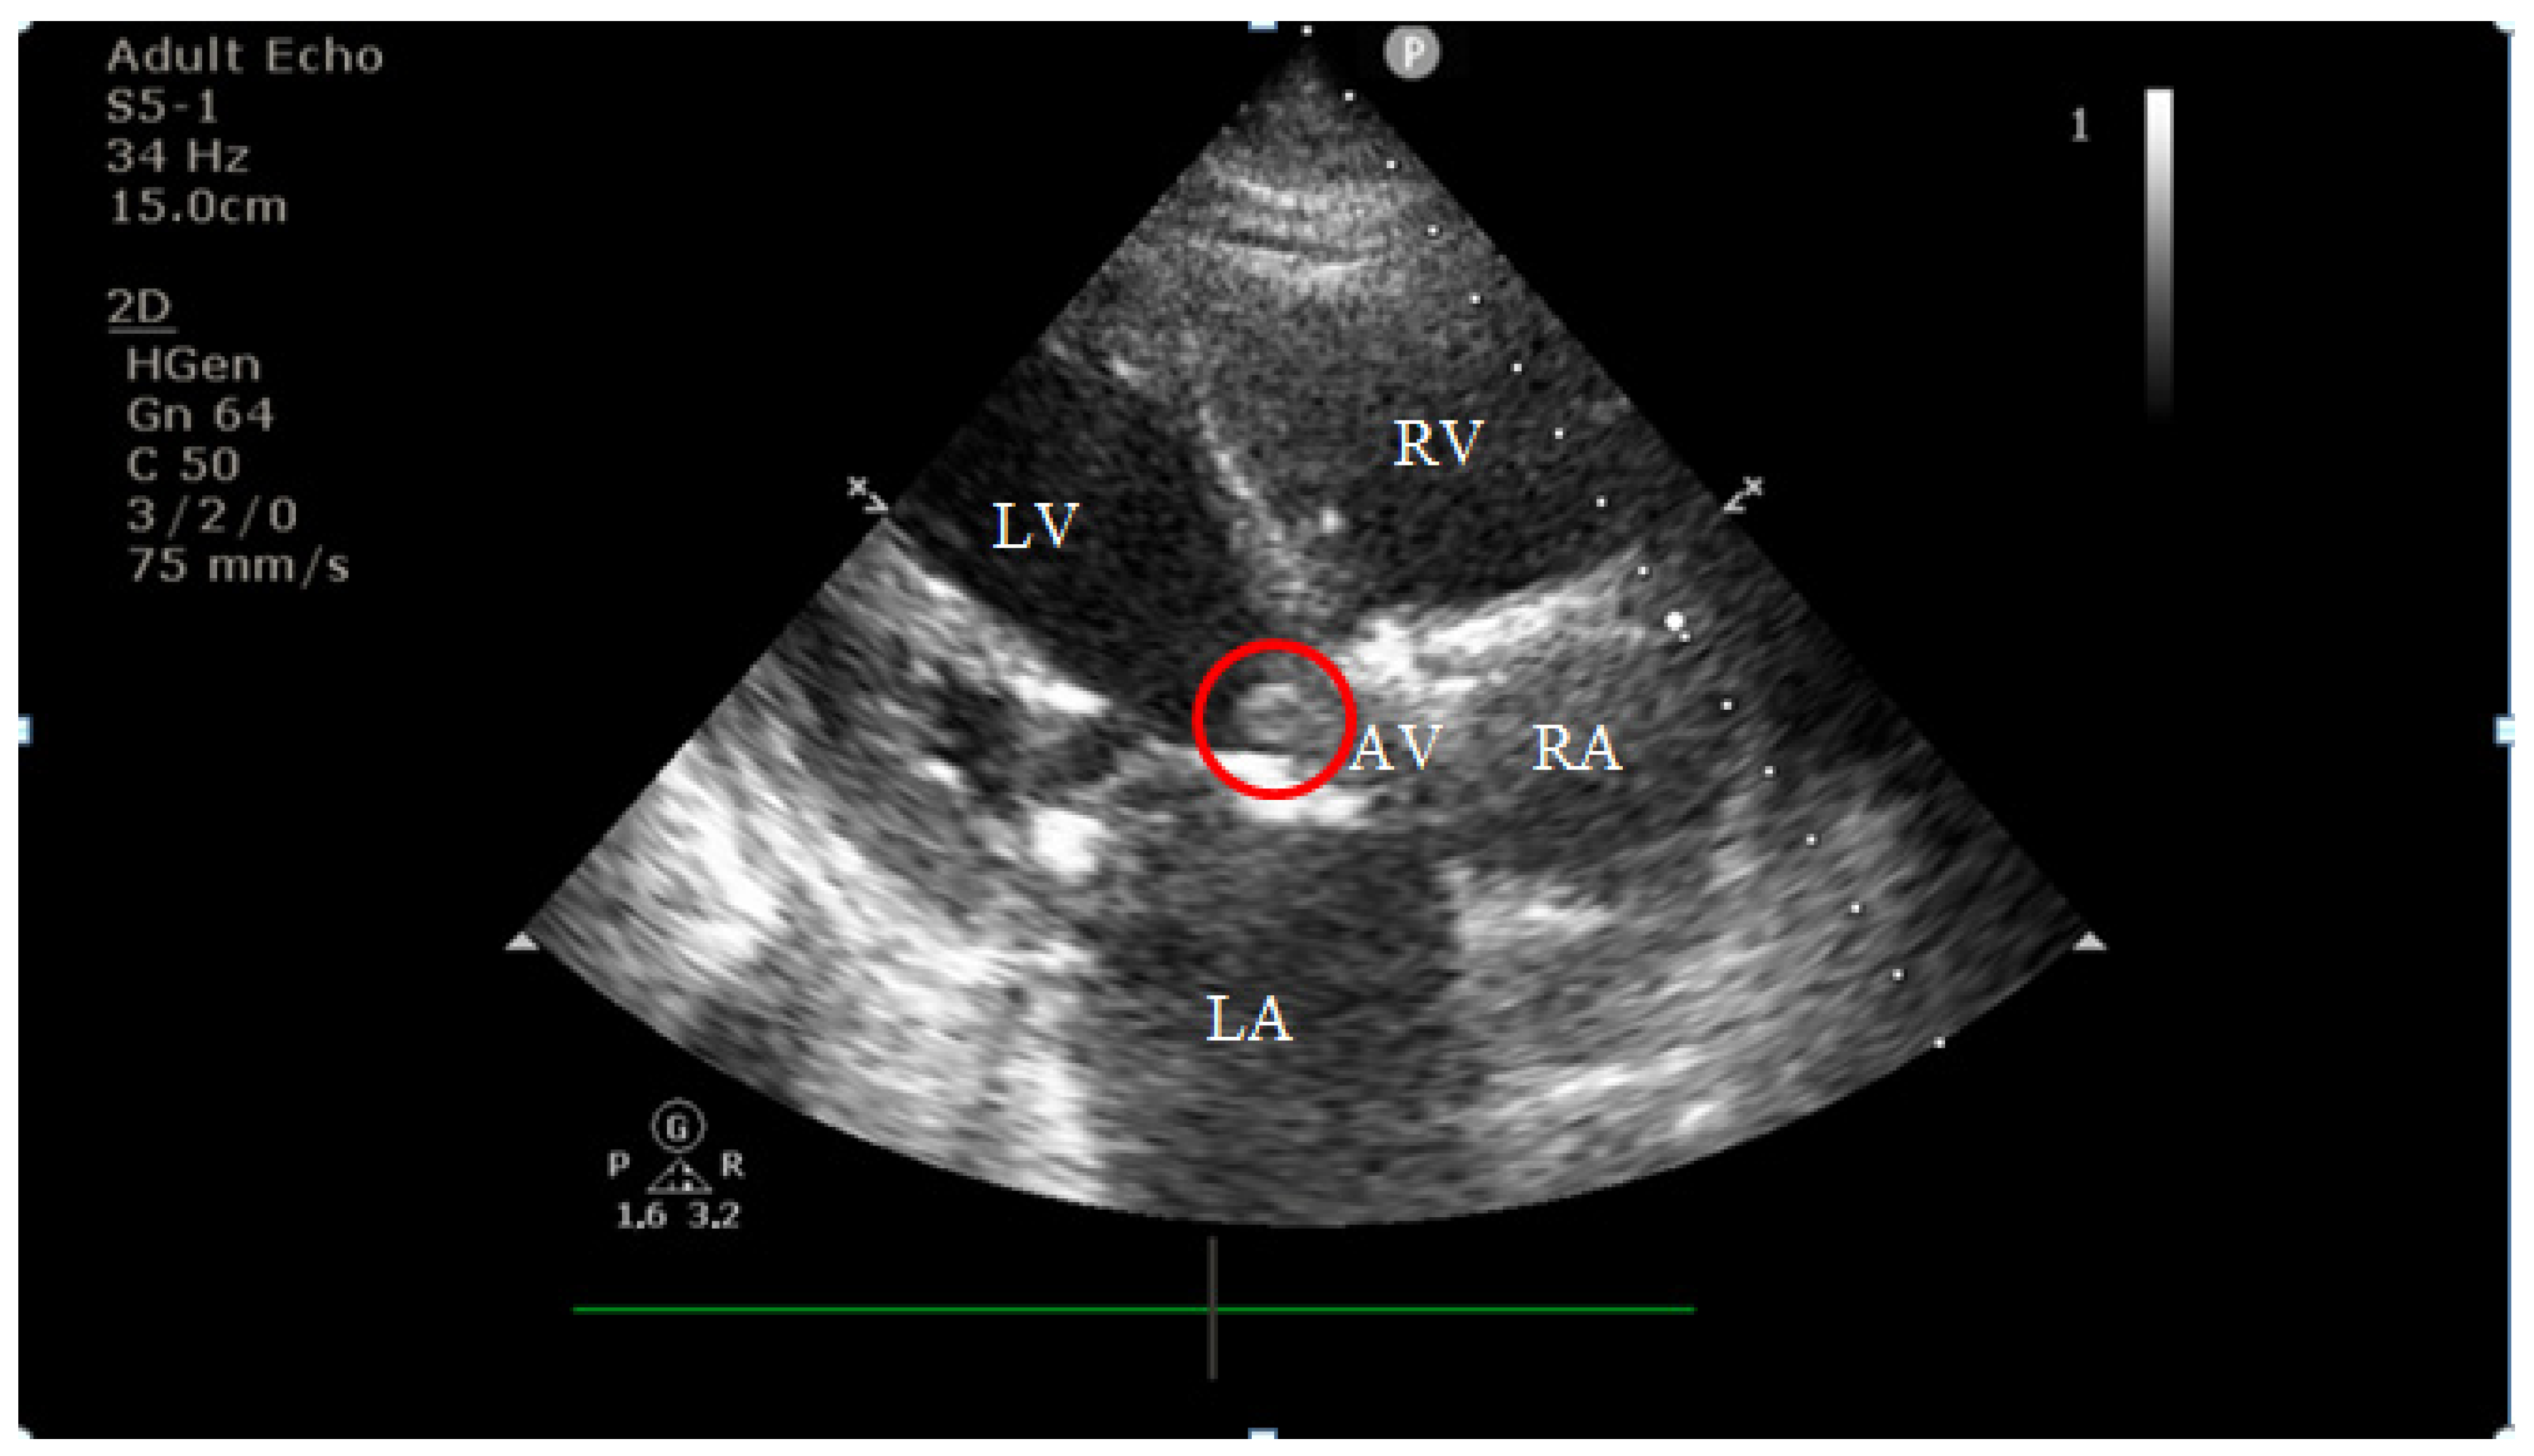

4.2. Diagnostic Findings: Mitral Valve Dysfunction and Embolic Phenomena

4.3. Coronary Complications and Diagnostic Dilemma